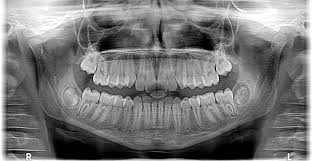

Las caries en los dientes de leche incrementa el riesgo de problemas de mordida

La caries en los dientes de leche también es importante Más de la mitad de los niños españoles de entre 4 y 13 años han tenido […]